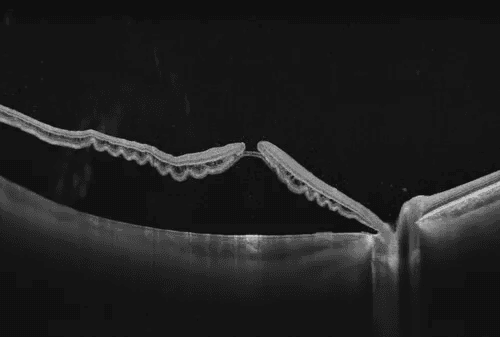

Swept-source OCT with full-range imaging capability, offering 12mm posterior scan depth and 15mm anterior scan depth with sub-6 micron optical resolution, utilizing 1060nm wavelength technology for improved penetration through cataracts and vitreous opacities

Anterior Segment:

Scan depth: 15mm

Maximum line scan length: 24mm

Full-range imaging without separate anterior/posterior switching